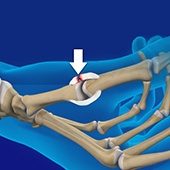

Trigger Finger

Inflammation in the tenosynovium leads to a condition called trigger finger, also known as stenosing tenosynovitis or flexor tendonitis, where one of the fingers or thumb of the hand is caught in a bent position. The affected digit may straighten with a quick snap, like pulling and releasing the trigger on a gun, hence the name trigger finger.